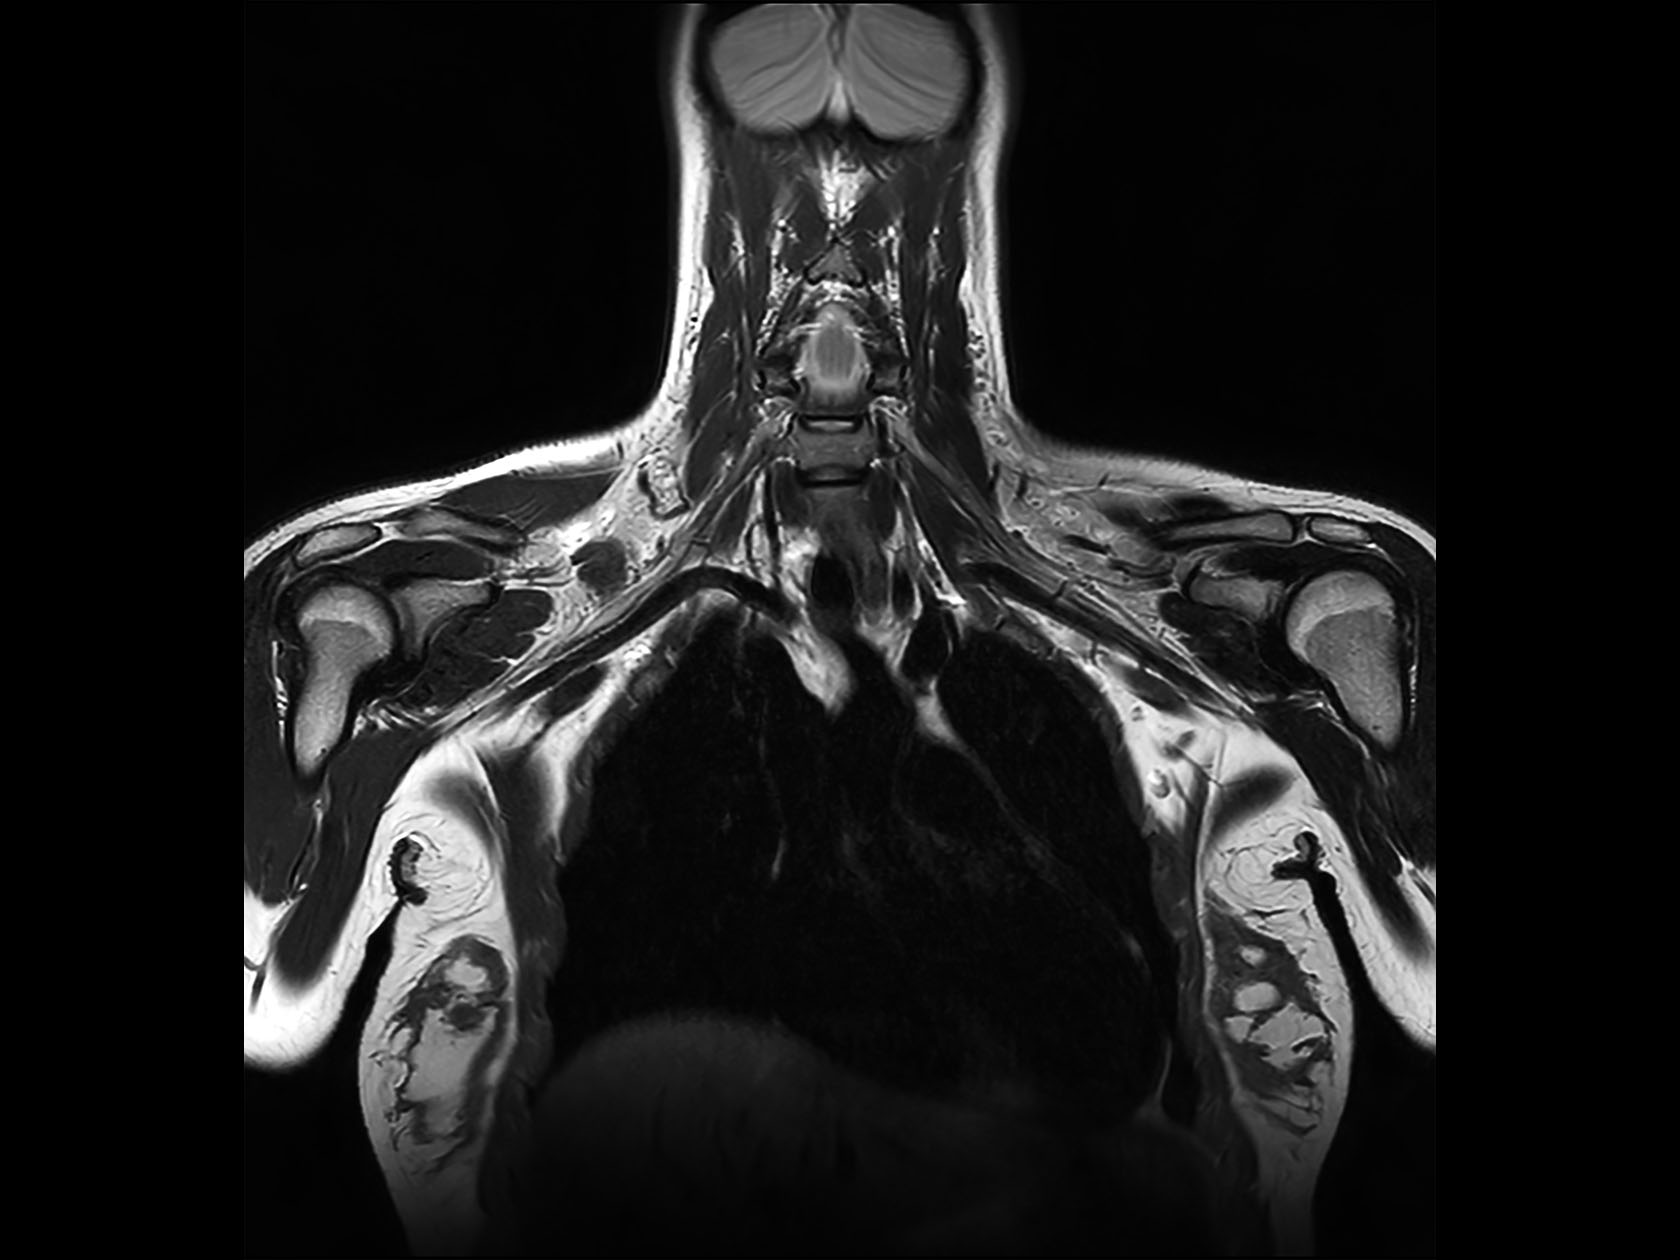

Non-invasive nerve plexus imaging

• Clinical Application